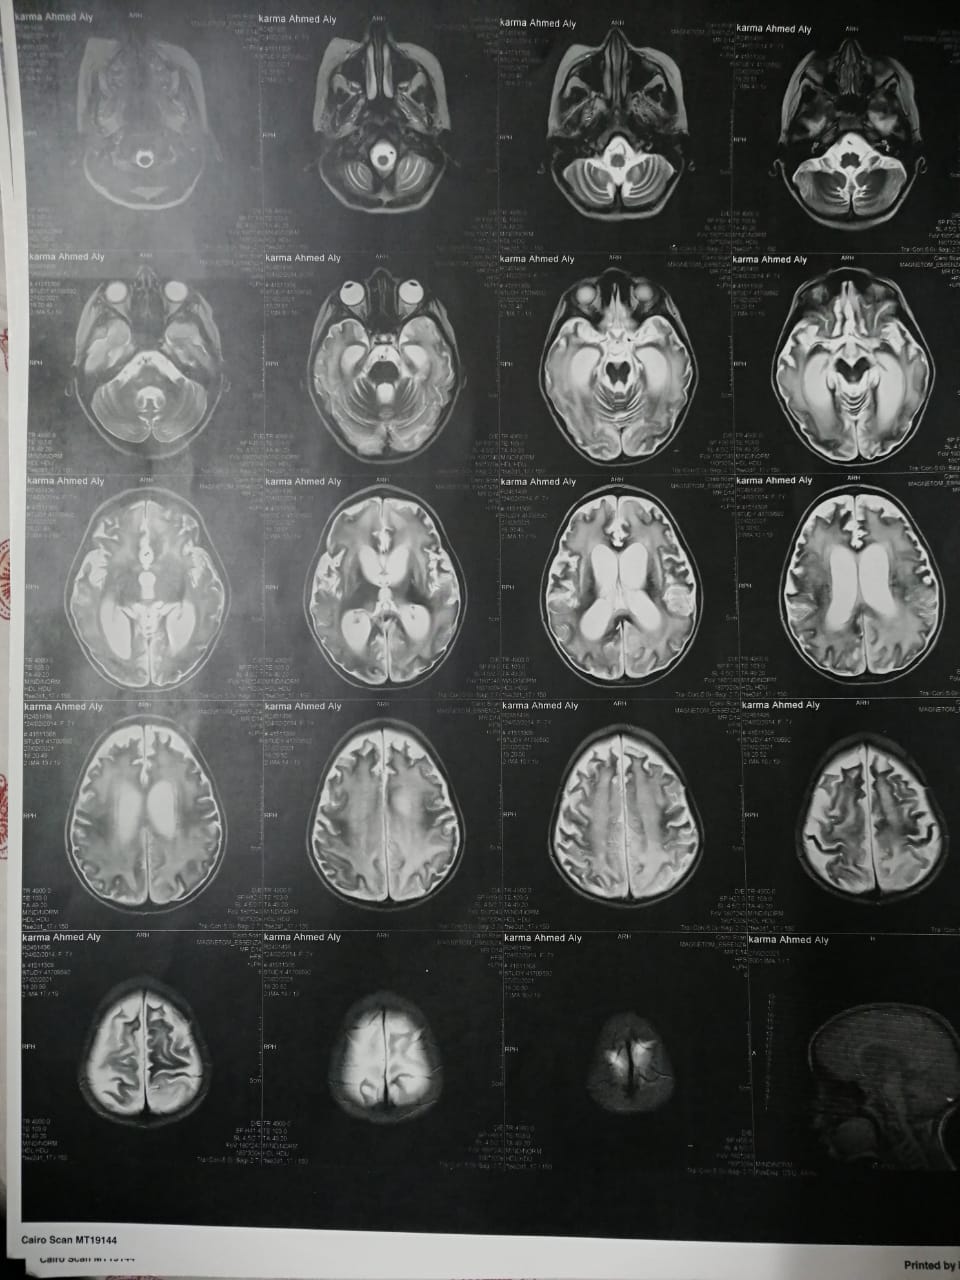

استغاث أحمد علي، بالمسؤولين، لعلاج ابنته صاحبة الـ7 سنوات، المصابة بضمور شديد في المخ، موضحا أن ابنته كانت تعاني من ارتفاع ضغط الشريان الرئوي، وأثناء علاجها أشارت طبيبتها بدواء خاطئ، أدى إلى إصابتها بضمور في المخ.

وأشار إلى أنه بعد خروج كارما من المستشفى تم إجراء فحوصات أخرى عليها، تبينت عدم التطابق بين التقارير الطبية لها بداخل المستشفى والفحوصات الجديدة.

وقال علي: "بنتي جالها ضمور في المخ وفي كل الحواس، بسبب الدوا الغلط، بنعملها علاج طبيعي بيتكلف في الشهر 20 ألف جنيه"، مشددًا": "هي بتفتح عينها بس".